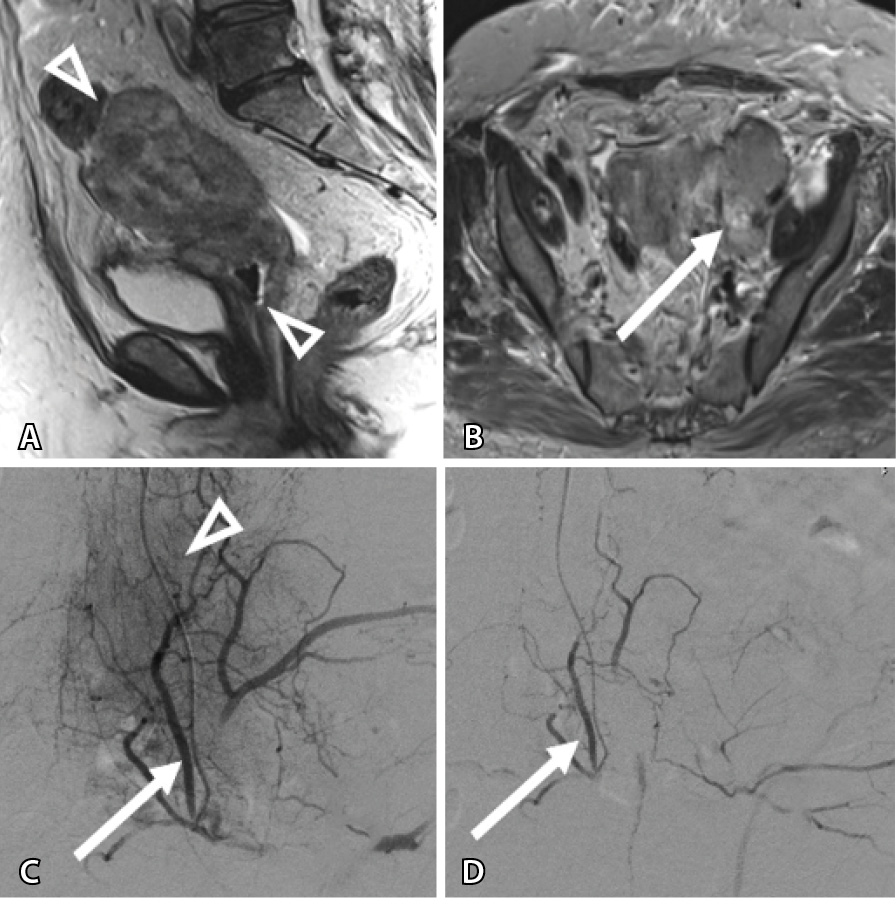

Вместе с тем изменения, происходящие внутри опухоли, влияли на тактику ведения пациенток. Так, за счет уменьшения толщины опухолевой массы в 17% всех случаев (n = 17) формировались участки истончения стенки органа до 1,5–2 мм (рис. 2), что потребовало коррекции сроков хирургического лечения.

Рис. 2. Женщина 31 года, первичный рак шейки матки: А – магнитно-резонансная томография в сагиттальной проекции: опухоль с инфильтративным ростом, вовлекающая шейку матки, нижнюю половину тела матки, передний свод влагалища (треугольные стрелки); Б – этап трансартериальной химиоэмболизации: на ангиограмме определяется сеть опухолевых афферентов (треугольная стрелка), отходящих от маточной артерии (стрелка); В – результат эмболизации: опухолевые афференты не контрастируются, проходимость маточной артерии сохранена (стрелка); Г – магнитно-резонансная томография в сагиттальной проекции через 14 дней: уменьшение протяженности и толщины опухоли (треугольные стрелки) с резким истончением стенки переднего свода влагалища (стрелка)